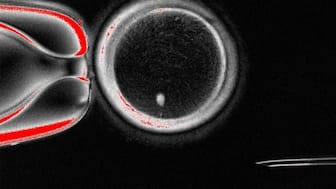

An image of an oocyte with a bright image of a skin cell nucleus before fertilisation.  Image courtesy: Oregon Health & Science University